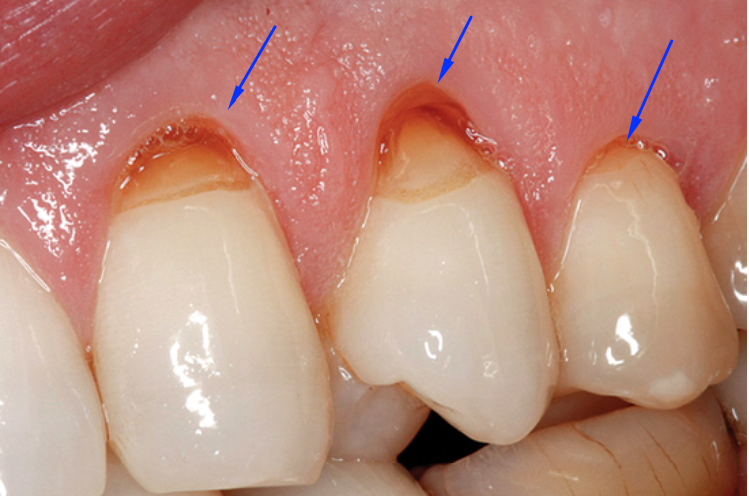

En este caso que les acabo de comentar el paciente presenta lesiones no cariosas. Es una lesión que la podemos ver en el cuello de la corona de los dientes que se ve así:

Lo que ven allí es la dentina (segunda capa del dientes de afuera hacia adentro), porque se ha desgastado el esmalte 🙁

¿Recuerdas esa vieja canción que dice “los dientes de abajo se cepillan hacia arriba y los dientes de arriba se cepillan hacia abajo”? Pues éste paciente definitivamente no siguió el consejo de la canción. Seguramente se ha cepillado de derecha a izquierda con un cepillo de cerdas duras causando abrasión al cepillarse lo que ha traído como consecuencia la perdida del esmalte a nivel del cuello como lo he mostrado en la fotografía de arriba.